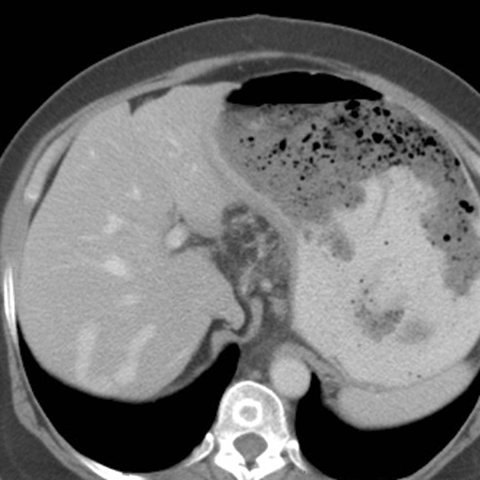

56 year-old male presents with abdominal pain and weight loss [4 of 5]